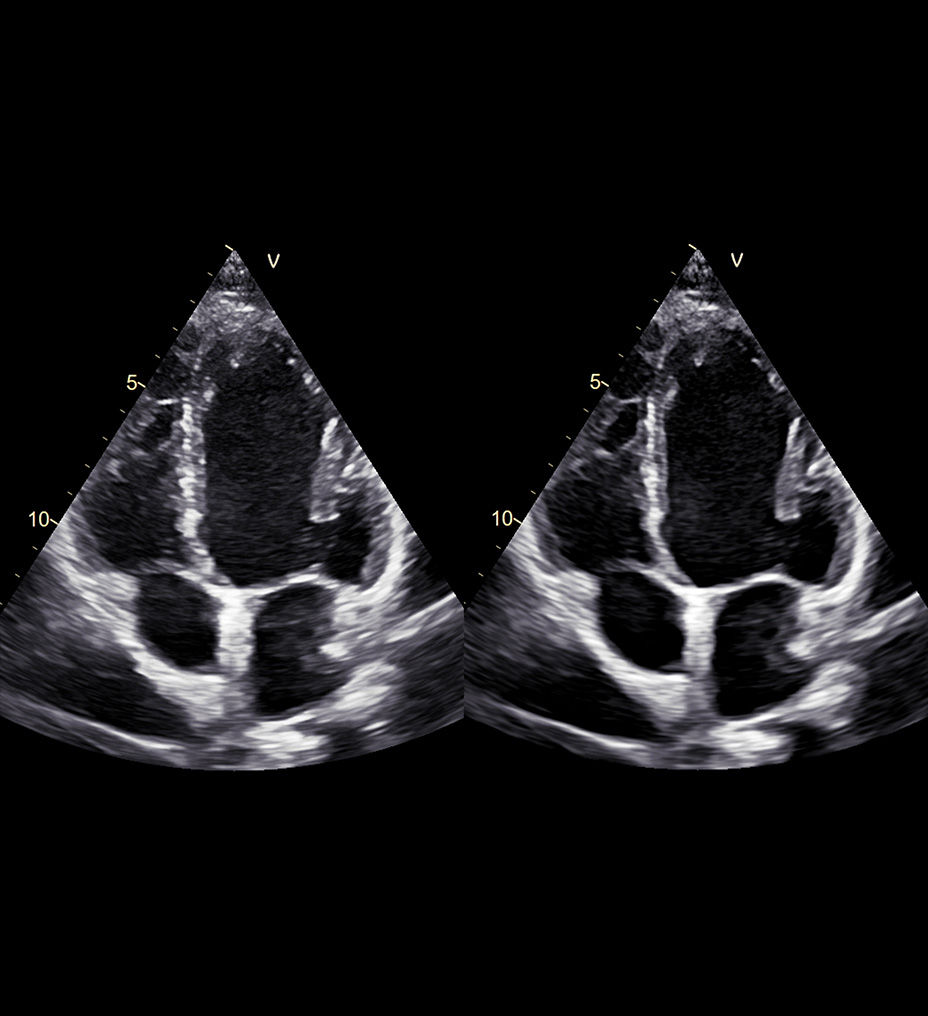

Sharp images, instant clarity

Discover extraordinary image clarity and precision

Designed to take you further, next-generation cSound Pioneer works in harmony with our sophisticated probe technology to deliver enhanced detail, a new level of Color Flow, and incredible 4D imaging for clinical confidence from the first scan.